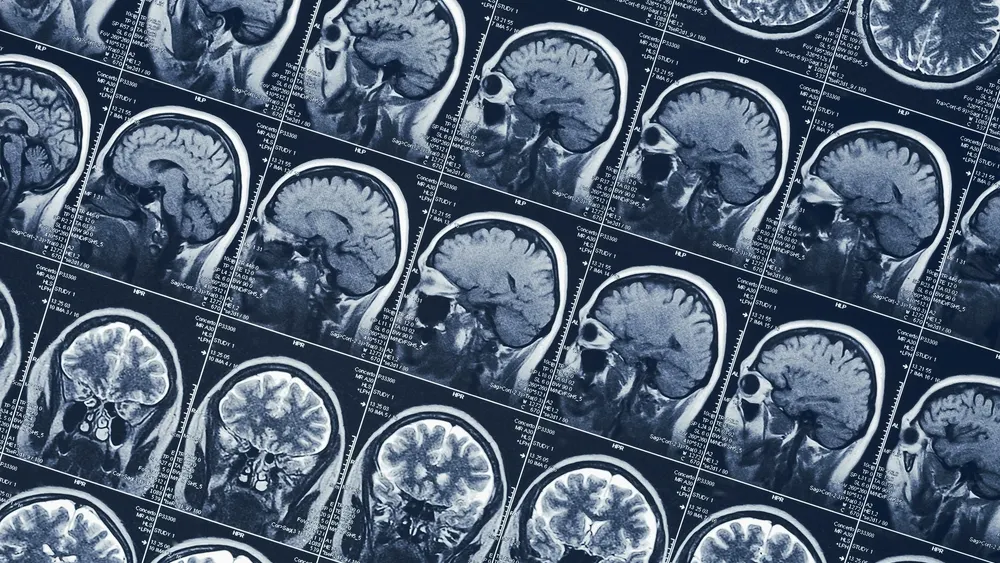

Врач объяснила, как вовремя обнаружить рак мозга

Гастроэнтеролог Анастасия Тимощенко рассказала, что протекающую бессимптомно начальную стадию рака мозга можно диагностировать по головным болям и ухудшению зрения.

В интервью NEWS.ru она раскрыла конкретику сигнализирующих о начавшемся раке мозга симптомах: это выпадение полей зрения или изменение светочувствительности.

Головная боль, по мнению врача, характерна для крупных образований головного мозга. Интенсивность головной боли зависит от размера и местоположения опухоли. Но если голова болит часто, а медикаменты не помогают, это уже серьезный повод обратиться к неврологу и провести дополнительное обследование.

Не стоит оставлять без внимания такие явления, как нарушение координации и трудности с удержанием равновесия, а также даже самые небольшие эпилептические припадки.